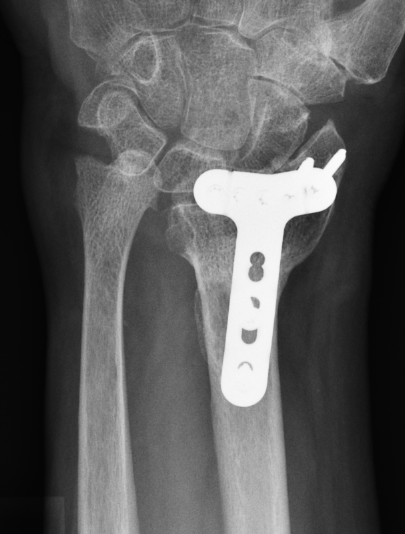

Flexor tendon rupture

Etiology

Plates distal to watershed mark

Prominent screws

Thicker plates

Incidence

Asadollahi et al J Orthop Traumatol 2013

- systematic review of flexor tendon rupture after plating of distal radius fractures

- 47 cases

- FPL 57%

- FDP to index finger 15%

Volar rim plates

Lari et al Eur J Orthop Surg Traumatol 2023

- systematic review of surgical treatment of volar rim fractures

- 26 studies and 600 patients

- implant removal 22%

- flexor tendon irritation 6%